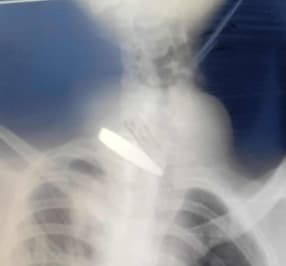

Liknande text är mejlad till sjukvårdsminister Elisabet Lann. Bilden är en preoperativ röntgen från en av de drabbade i artikeln. Flera tidningar har nekat publicering av denna text.